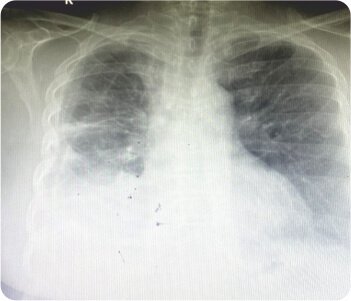

Chest radiograph showing right apical bullae

On initial evaluation, X-ray was found to be radiolucent in right upper and lower zone suggestive of right sided pneumothorax. 2D Echo revealed concentric LVH / no rwma. CT chest (plain) revealed gross right pneumothorax with mild tracheal shift to left possibly due to rupture of emphysematous bullae. Subpleural emphysematous changes were noted in left lung with large bullae on both sides. Patient was taken up for emergency thoracostomy under aseptic conditions with the chest tube placed in the right 4th intercoastal space. Post procedural CXR was taken, ICD was in place. During the hospital stay, patient was closely monitored for desaturation and patient was put on oxygen support, antibiotics, nebulization, thyroid medication. Repeat CT chest revealed ICD in place with right gross pneumothorax with sub pleural bullae/ cysts projecting into pneumothorax and multiple cysts of varying sizes and para septal emphysematous bullae in left lung. Alfa 1 antitrypsin levels were normal. Patient was diagnosed as a case of B/L bullous lung disease with spontaneous right sided pneumothorax.